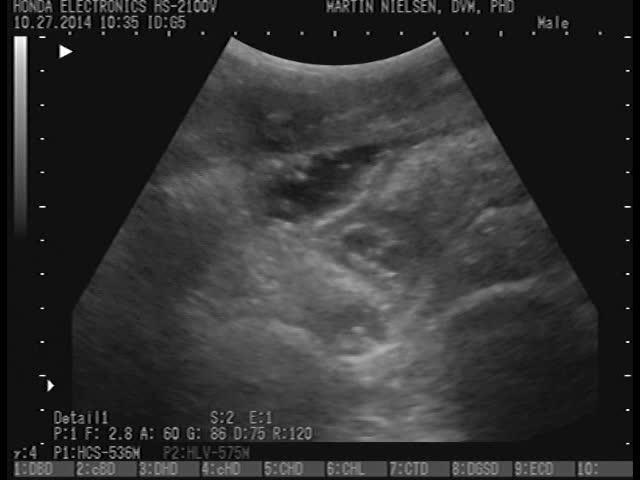

Ascarid parasites visualized within small intestinal loops by transabdominal ultrasonography in a naturally infected foal.

Courtesy of Dr. Martin K. Nielsen.